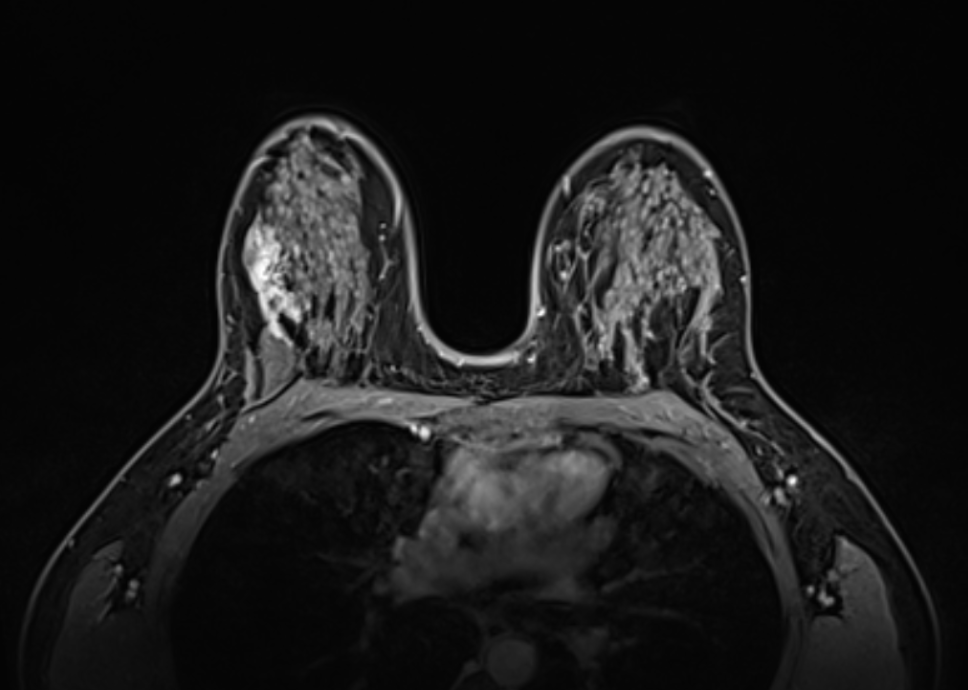

Затем были проведены рентгеновская маммография и МРТ молочной железы.

В результате исследований у пациентки был диагностирован пролиферативный DCIS правой молочной железы (протоковая карцинома молочной железы in situ).